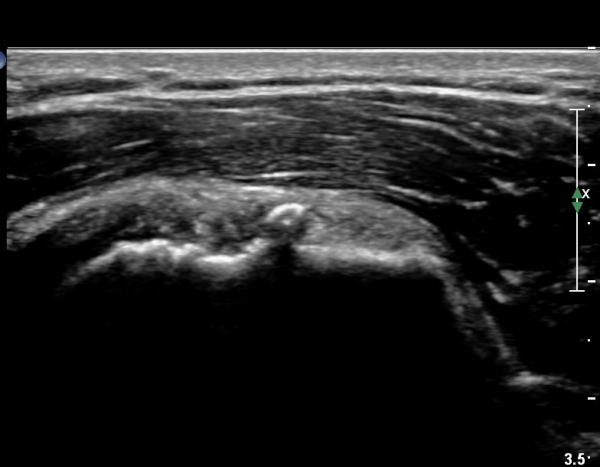

°ß°©ÇÏ±Ù°Ç ÁߺΠÁ¾´Ü¸é°Ë»ç¿¡¼­ ƯÀÌ ¼Ò°ßÀ» º¸ÀÌÁö ¾ÊÀ¸³ª(»çÁø 2) ŽÃËÀÚ¸¦ Á¶±Ý ÇϹæ(´Ù¸®ÂÊ)

À¸·Î À̵¿ÇÏ´Ï °ß°©Çϱٰdz»  ¼®È¸È­ µ¢¾î¸®°¡ °üÂûµÈ´Ù(»çÁø 3).

°ß°©ÇÏ±Ù°Ç È¾´Ü¸é°Ë»ç»ó ¼Ò°áÀý ÇÊÁú°ñº¯È­¿Í °ß°©ÇÏ±Ù°Ç Áߺο¡ °í¿¡ÄÚ µ¢¾î¸®°¡ °üÂûµÇ°í

¼®È¸ À§ÂÊ(¸Ó¸®ÂÊ)ÀÇ ÈûÁÙÀÇ Àú¿¡ÄÚ º¯È­°¡ °üÂûµÈ´Ù(»çÁø 4, 5).